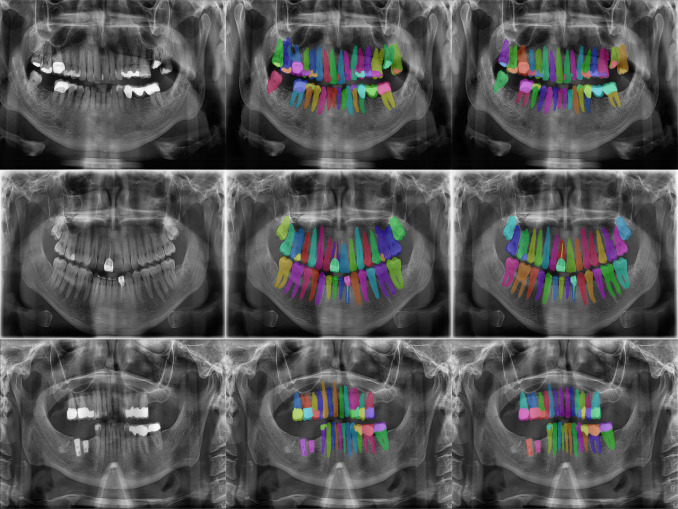

• 01.

Teeth health detection

Radiographic images are annotated by human experts, and used to teach AI what healthy and unhealthy teeth look like and how to recognize the differences.teeth